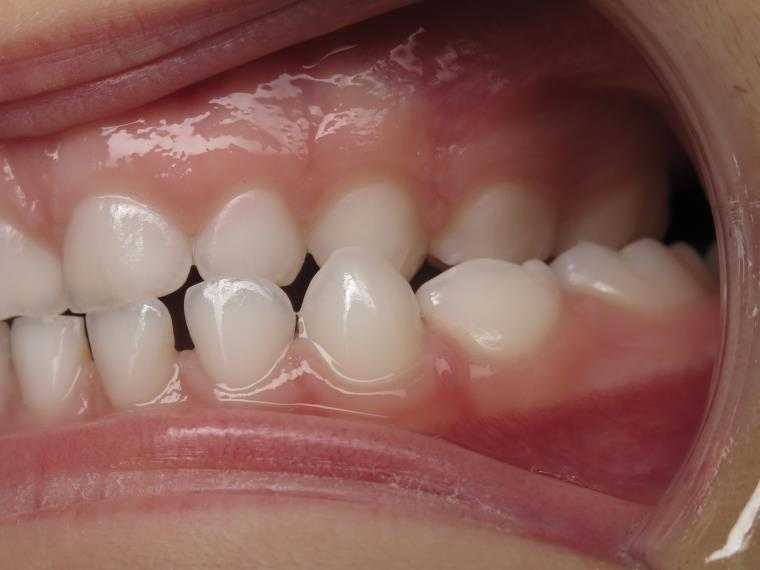

bilan début et en cours de traitement